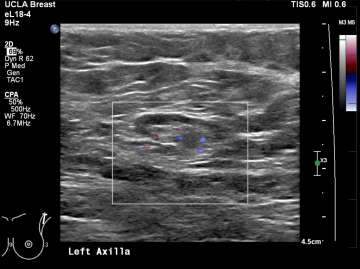

Features concerning for malignancy include round shape, increased cortical thickness and loss of fatty hilum1. The relationship of the lymph node cortex to hilum can be used to classify lymph node morphology and likelihood of malignancy. As the cortical thickness increases, there are reciprocal changes in the hilum beginning with hilar effacement and progressing to absence or replacement of the lymph node hilum2,3. Cortical thickening (figure 3) is considered the earliest morphologic change associated with malignancy; however, this finding is nonspecific with a low positive predictive value1-3. Absent/replaced hilum (figure 4) is the most specific for malignancy with a positive predictive value of 58-97%2.

Case: Axillary Lymphadenopathy  Figure 4

Figure 4. Enlarged right axillary lymph node with loss of fatty hilum. Biopsy recommended.